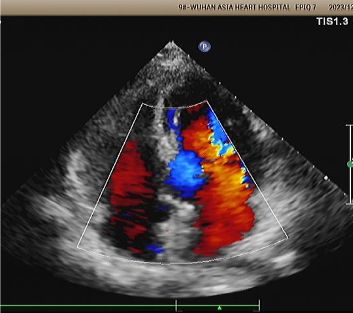

Eco de 1 ano:

No visible disc structures – replaced by 8mm tissue thickening at the septal implant site.

Zero residual shunt (rest or post-Valsalva).

Absorção completa do dispositivo confirmada.